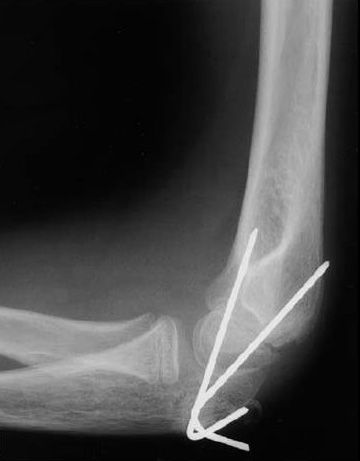

Elbow fracture treated with pins

This X-ray shows a child’s elbow fracture that has been put into the correct position and held in place with two pins. The pins will be removed after healing has begun.

Reproduced from: Surgical management of pediatric fractures in the upper extremity, Flynn J, Sarwark J, Waters P, Bae D, Lemke L: Instr Course Lect 2003, 54: 635-645.